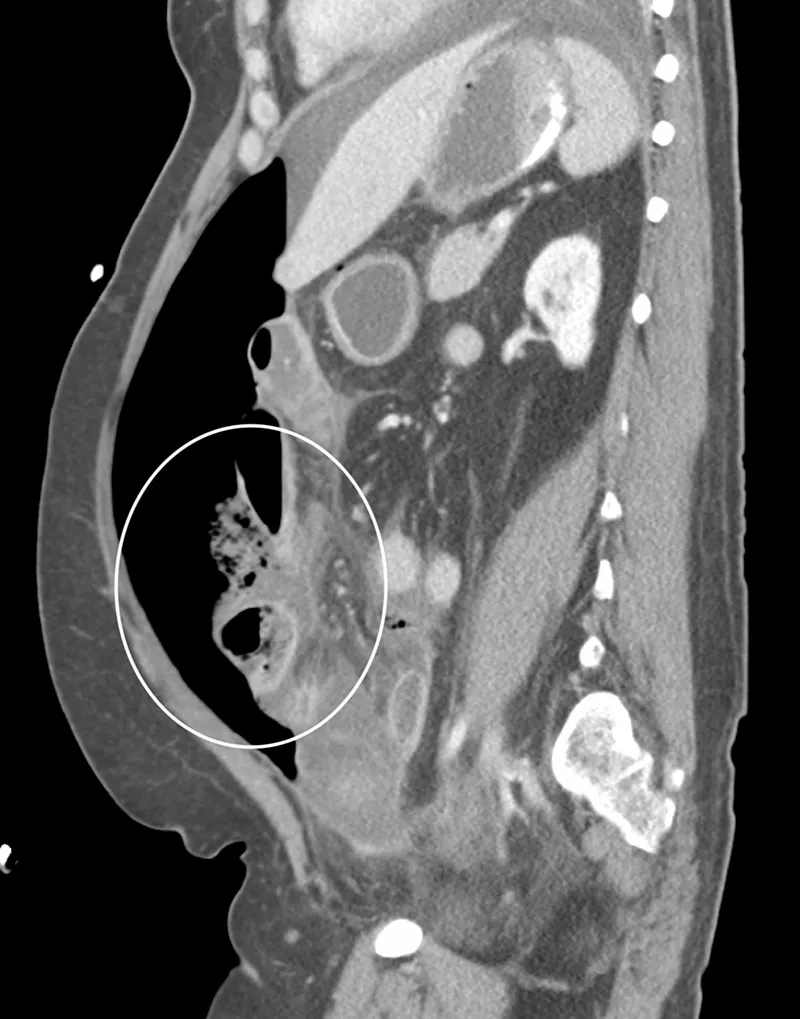

- USG: Fluid, abscesses, organ-specific (e.g., appendicitis, cholecystitis).

- CT (Contrast): Gold standard for source, extent, complications.

- Percutaneous Drainage (PCD): For localized abscesses.

- Intra-abdominal abscess: Percutaneous drainage (USG/CT guided) is often treatment.